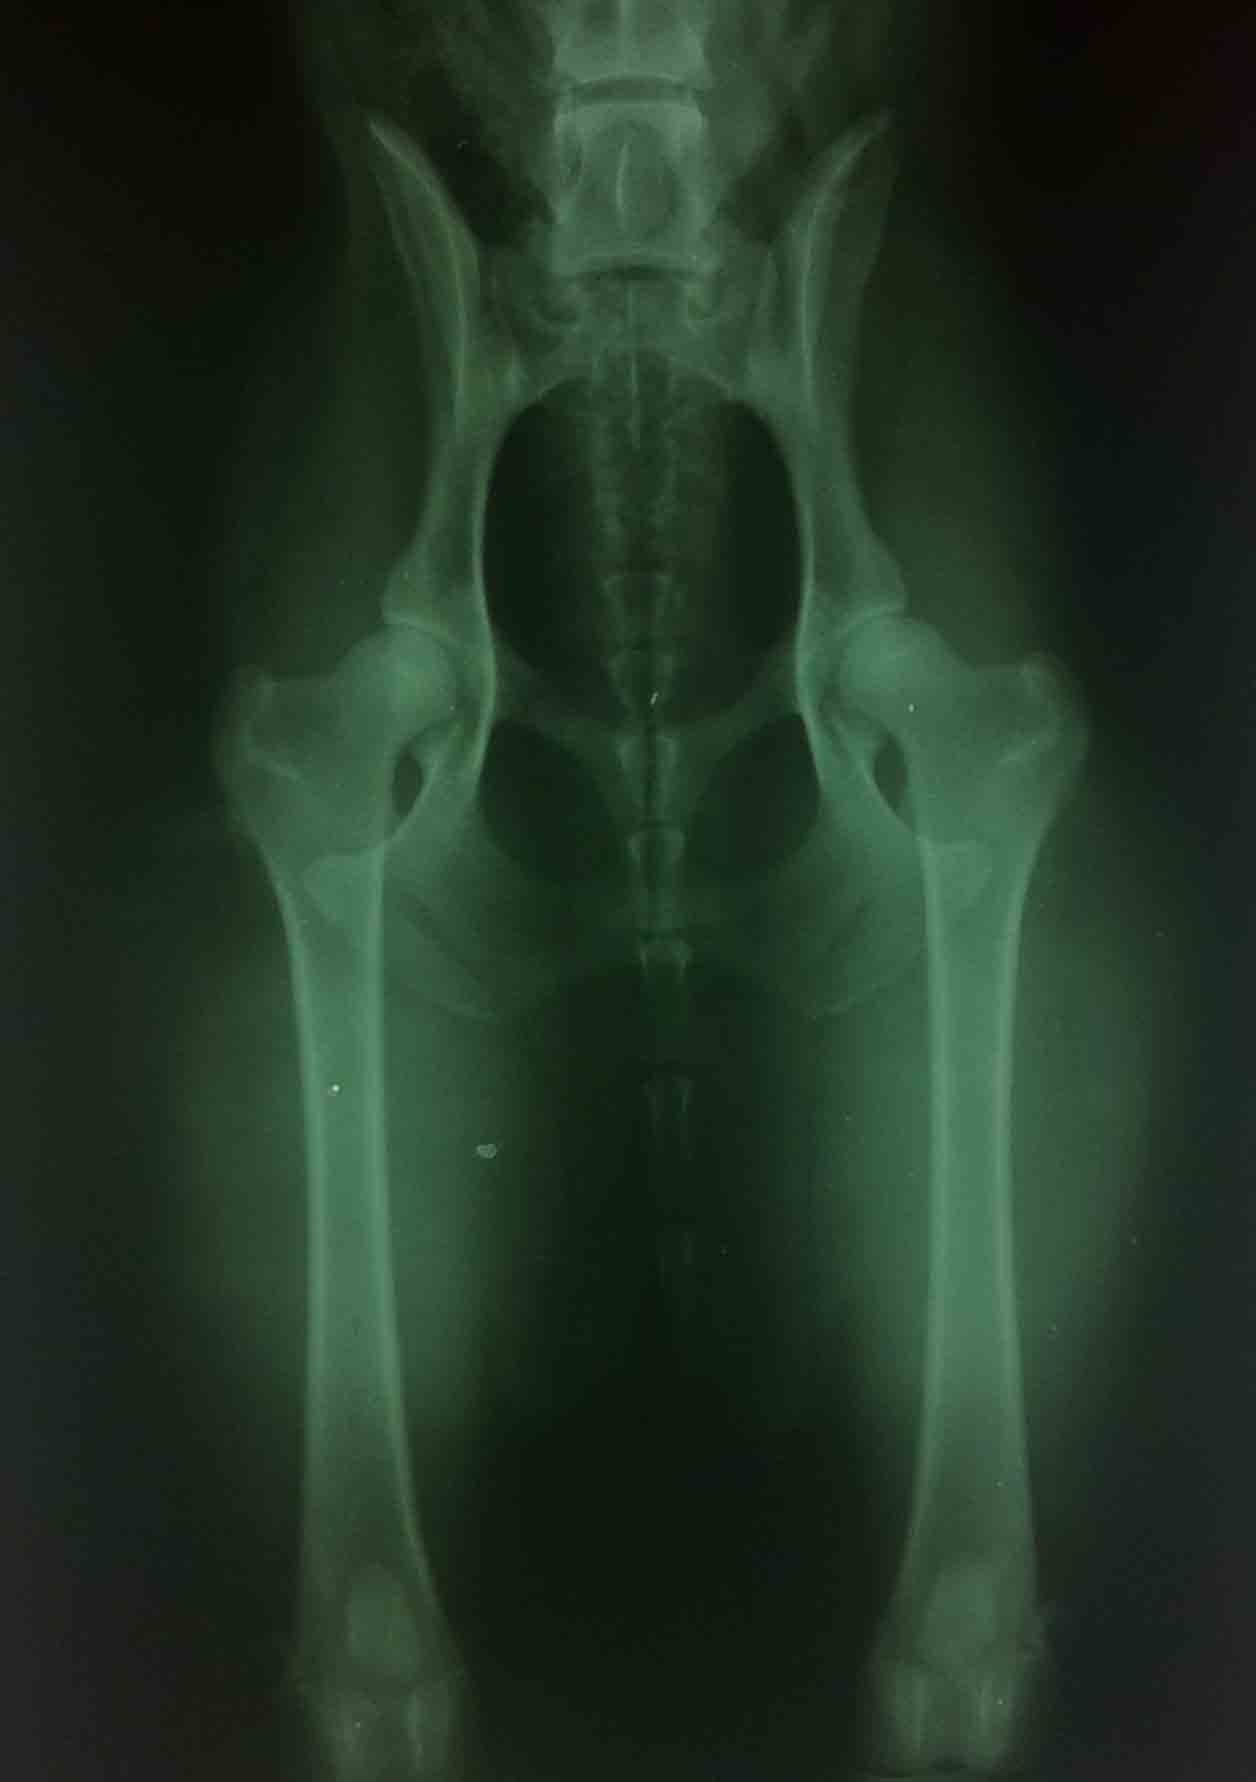

CARRA byla na vyšetření dysplazii kyčelních kloubů s krásným výsledkem

Bez příznaků DKK A

Páničce Magdě moc gratulujeme!